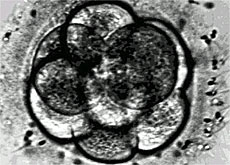

قد يبدو الخبَـر غريبا للوهلة الأولى، ولكنها الحقيقة. لقد أصبح العِـلاج بالتلقيح الاصطـناعي مُـتاحا في بعض دول إفريقيا بتكاليف زهيدة، لا تزيد عن 300 دولار، وذلك بفضل المؤسسة السويسرية "Low Cost IVF Foundation"، التي مقرّها في مدينة لوغانو، جنوب سويسرا، والتي تقوم بتمويل مجموعة من المراكز المتخصِّـصة في كل من تنزانيا وجنوب إفريقيا والسودان.

“فعلى سبيل المثال، قُـمنا باستخدام بعض العقاقير الرخيصة في تحفيز المبايض، بدلا من بعض أشكال مستحضرات هرمون “gonadotropin” المُـستخدمة في العيادات الغربية، وباستبدال الحاضنات المجهّـزة بثاني أكسيد الكربون، والمستخدمة لزراعة الأجنة قبل نقلها إلى الرّحم، بعُـلب أو “كبسولات” بلاستيكية مُـحكمة الإغلاق”.